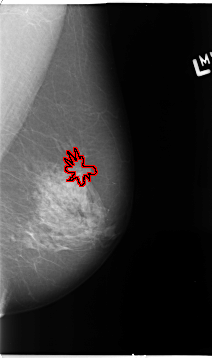

B_3093_1.LEFT_MLO

B_3093_1.LEFT_CC

LEFT_CC LINES 4656 PIXELS_PER_LINE 3016 BITS_PER_PIXEL 12 RESOLUTION 50 OVERLAY

LEFT_MLO LINES 4648 PIXELS_PER_LINE 2744 BITS_PER_PIXEL 12 RESOLUTION 50 OVERLAY

FILE: B_3093_1.LEFT_CC.OVERLAY

TOTAL_ABNORMALITIES 1

ABNORMALITY 1

LESION_TYPE MASS SHAPE ARCHITECTURAL_DISTORTION MARGINS ILL_DEFINED

ASSESSMENT 4

SUBTLETY 3

PATHOLOGY BENIGN

TOTAL_OUTLINES 1

BOUNDARY